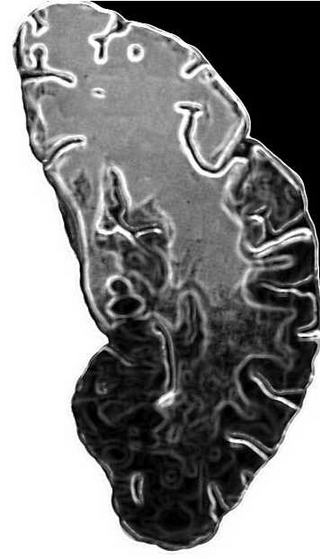

А теперь собственно эксперимент: попытка нейрофизиологов «заглянуть в мозг» в момент умственного напряжения. Регистрируется электроэнцефалограмма у людей довольно зрелого возраста при тестировании на способность к запоминанию. Они уже разделены предварительным тестированием по способности запоминать заданную информацию. Один из главных показателей ЭЭГ — альфа-ритм — ведет себя по-разному у более и у менее «памятливых». Отмечено его более резкое уменьшение и даже исчезновение у испытуемых, не способных к полному запоминанию теста. Но точно так же ведет себя альфа- ритм в моменты тревоги и стресса у любого из нас. Возможно, у многих реакция мозговых зон на умственную нагрузку в стесненных рамках тестирования вызывает торможение типа тревожно-стрессового и ограничивает усвоение знаний? В таком случае это не приговор к отставанию и «снятию с дистанции». Если создать для них индивидуальную программу без давления цейтнота и оценочного пресса, с заменой внешнего контроля на самопроверку, человек сможет запоминать и усваивать.

Итак, можно ли инструментально измерить разницу между «обученным» и «необученным» мозгом на уровне морфологии и физиологии? А может, и философии? И что входит в само понятие обученности мозга? Тут обнаруживается, что проблема поставлена не впервые. Профессор Сергей Чепурнов припоминает, как лет тридцать назад ученые советы отклонили защиту одной диссертации, автор которой сообщал об обнаруженном росте межнейронных контактов в мозге собаки, обученной рефлексам по И.П. Павлову. Такую «антинаучную ересь» тогда даже не приняли к рассмотрению. Теперь же директор знаменитого Института мозга РАМН профессор Г.Д. Смирнов высказывает догадку, что межклеточные «мостики» растут и меняют объем сами клетки...

Участники маленького «мозгового штурма» совершили экскурс в механизмы памяти, приоткрытые последними отечественными и зарубежными экспериментами. Профессор Алексей Латанов из МГУ показал уникальные кинокадры: радиотелеметрия позволила ему исследовать, что творится в гиппокампе голубя, потерявшего и нашедшего путь к голубятне. А вот движения глаз обезьяны при восприятии жизненно важной информации. Загадочно, почему мышь, освоившая путь в лабиринте, с трудом его находит после периода кормления жирной пищей. Что там, синапсные джунгли увядают от обжорства? Может, это еще одно предупреждение гурманам? А вот почти «живая» микроскопная картинка: химические нейромедиаторы вызывают в культуре мозга мыши тот же рост соединительных отростков между нейронами — аксонов с синапсами, который мы предполагаем и от обучения. Где здесь «курица», где «яйцо»?